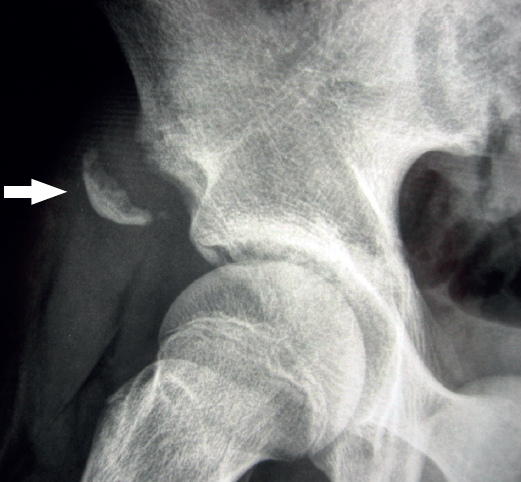

Si el dolor del paciente es muy proximal, es importante recordar que pueden producirse arrancamientos del tendón a nivel de su origen en la espina ilíaca anteroinferior (EIAI), con o sin avulsión ósea asociada (Figura 6).

Figura 6. Radiografía en proyección alar de la cadera derecha de un adolescente. Apofisiolisis de la espina ilíaca anteroinferior, por tracción del tendón del recto anterior del cuádriceps. La flecha señala el fragmento óseo avulsionado.